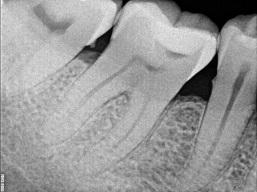

Если пульпит вовремя не вылечить, то возникает воспаление околокорневых тканей зуба, т.е. периодонтит. Он тоже может протекать остро (с болью) или хронически (безболезненно). Как правило, на этом этапе на рентгеновском снимке уже видны изменения в окружающей зуб костной ткани.

может протекать без симптомов и без боли. Время от времени в десне возле корня зуба может образовываться свищ, из которого выделяется немного гноя. Периодонтит может быть диагностирован по рентгеновским снимкам. На них видны изменения в тканях, окружающих верхушку корня. Такой зуб непременно нуждается в лечении, несмотря на то, что он не вызывает никаких симптомов.